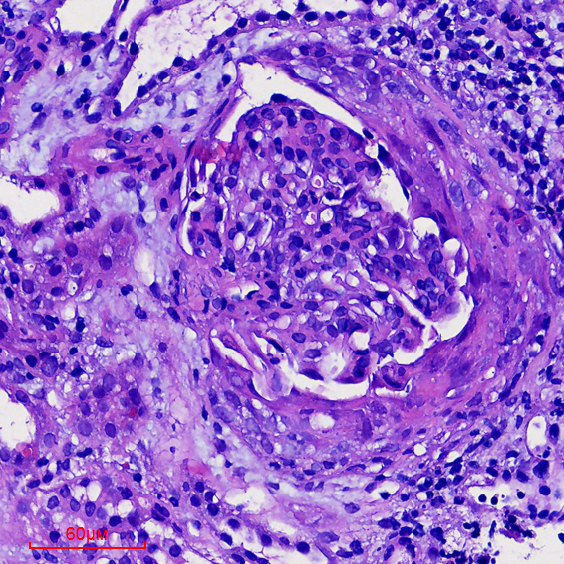

诊疗团队经过仔细的排查、多次讨论和查房,并与病理科陈虹主任医师、陶璇主治医师讨论肾脏病理改变后,考虑为过敏性紫癜合并免疫复合物介导的II型新月体肾炎

医讯怎么用『附一医讯』乱用偏方致过敏,女子急性肾衰竭!福建医大附一医院肾内科“换血救肾”_https://www.jmylbn.com_新闻资讯_第8张

▲肾小球新月体形成肾小管坏死

医讯怎么用『附一医讯』乱用偏方致过敏,女子急性肾衰竭!福建医大附一医院肾内科“换血救肾”_https://www.jmylbn.com_新闻资讯_第9张

▲肾小球新月体形成并间质有炎症细胞浸润